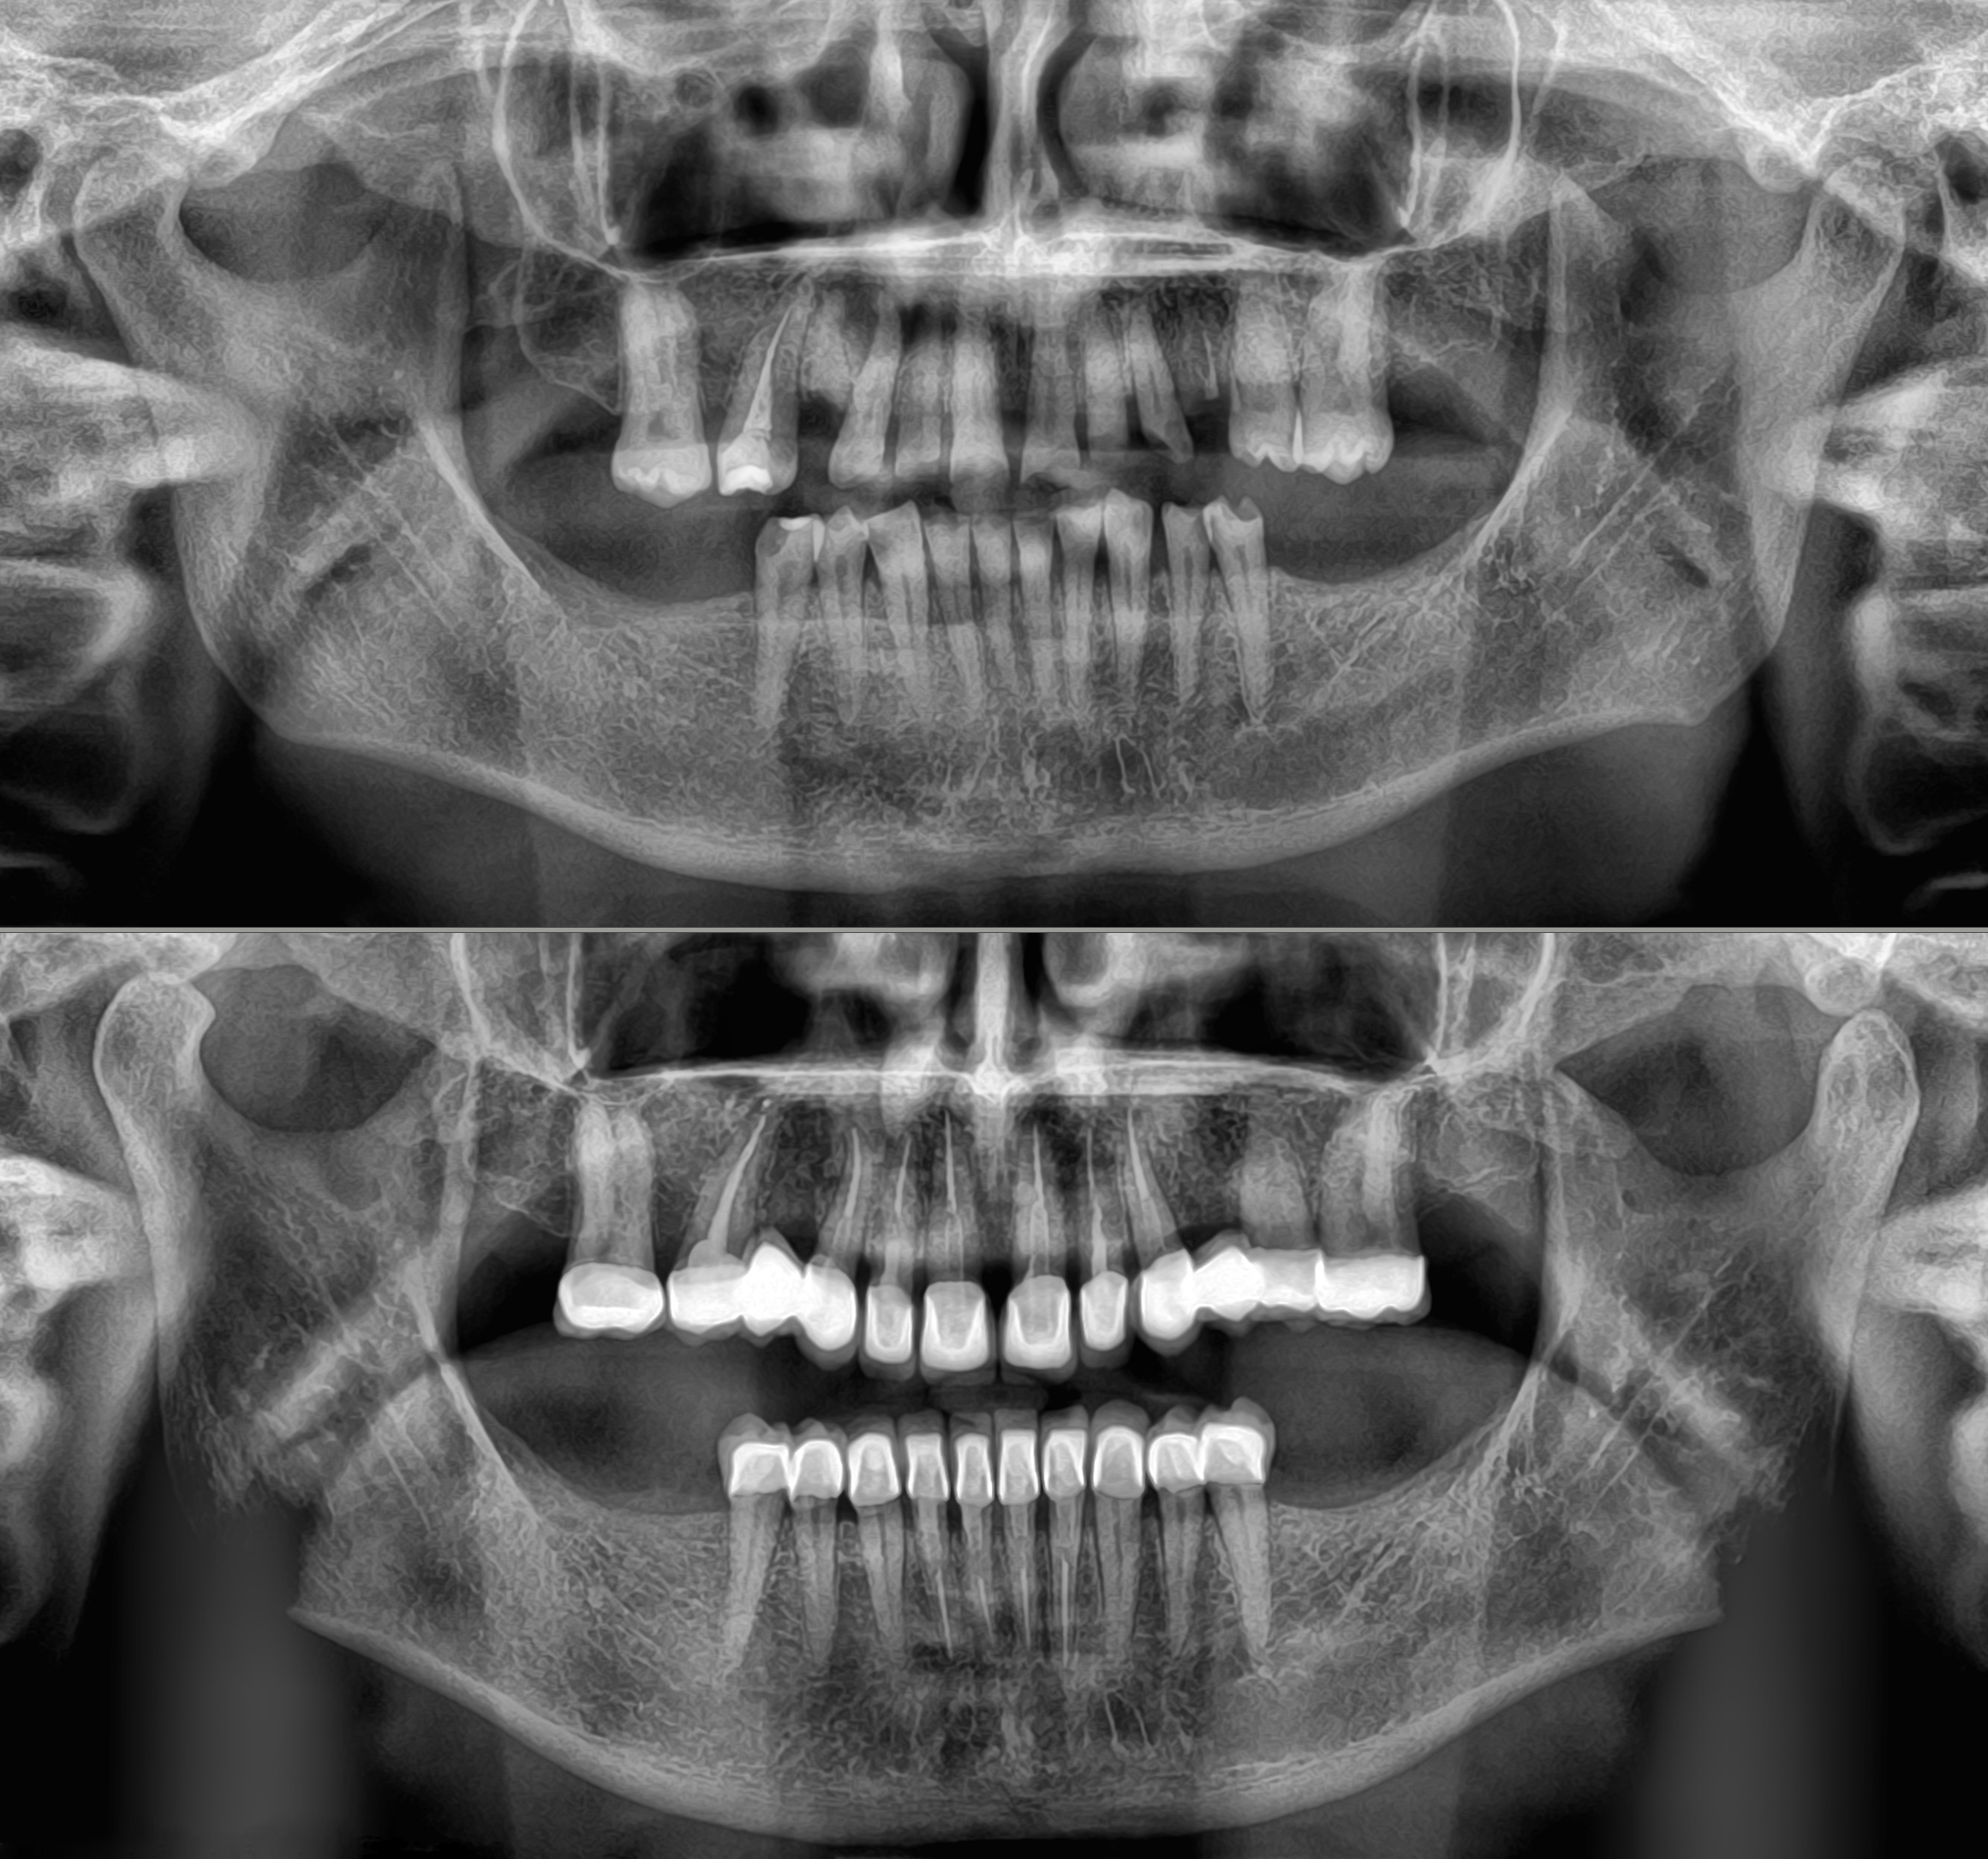

Ολική αποκατάσταση φθαρμένης και αποδιοργανωμένης οδοντοφυΐας με κεραμικές αποκαταστάσεις

Ασθενής με αποδιοργανωμένη, εκτενώς φθαρμένη οδοντοφυΐα, τερηδόνες και κατεστραμμένα δόντια στην άνω γνάθο που προκαλούσαν έντονους πόνους, προσήλθε στο Aesthetic Dental Studio στην Καλαμάτα με στόχο την αισθητική και λειτουργική αποκατάσταση του στόματός της.

Σε πρώτη φάση, αφαιρέθηκαν τα δόντια που ήταν πλήρως κατεστραμμένα, πραγματοποιήθηκαν ενδοδοντικές θεραπείες στα δόντια που μπορούσαν να αποκατασταθούν και έγιναν εμφράξεις σε δόντια με απλή τερηδόνα. Έτσι, το στόμα σταθεροποιήθηκε και ήταν πλέον έτοιμο για την δεύτερη φάση της θεραπείας, που περιελάμβανε την προσθετική αποκατάσταση των δοντιών.

Αφού όλα επιβεβαιώθηκαν, έγινε λήψη ψηφιακών αποτυπωμάτων με ενδοστοματικό σαρωτή και στην συνέχεια τοποθετήθηκαν ακίνητες κεραμικές αποκαταστάσεις ολικής επικάλυψης (στεφάνες και γέφυρες).

Το τελικό αποτέλεσμα ήταν αισθητικά άρτιο και λειτουργικά σταθερό, προσαρμοσμένο στις ανάγκες της ασθενούς.